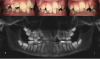

Fig 1. An 11-year-old girl presented with severe crowding and maxillary and mandibular hypoplasia. Previous recommendation was serial extraction of the remaining primary teeth and

the four bicuspids. The patient presented to the author’s practice office seeking alternative treatment for phase 1 utilizing expansion.

Figure 1

Fig 2. Pretreatment records.

Figure 2